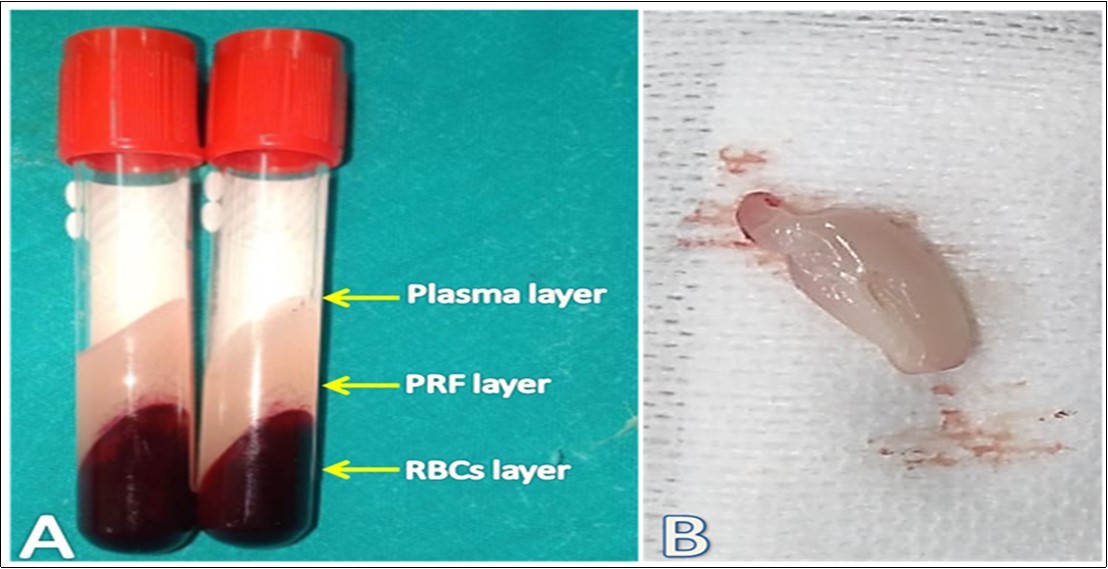

Preparation of Autogenous PRF Graft

Autogenous PRF was prepared from each rabbit as mentioned by Choukroun et al. 7 technique, where 3 mL of whole blood was obtained after aseptic preparation from the ear central or lateral veins of each rabbit in a 4 ml plain tube thereafter the blood was centrifuged immediately at a rate of 3000 rpm for 10 min till separation into three distinct layers. The fibrin clot in the middle layer (Figure 1), is considered the leukocyte-rich PRF which is carefully taken by non-toothed tissue forceps and separated from the RBCs layer with avoidance of the PRF membrane rupture.

Figure 1.Preparation of autogenous PRF. A: The blood in a plain tube was separated into three distinct layers where the middle layer, a strong fibrin clot, represents the leukocyterich PRF. B: A clean yellowish white PRF clot was obtained after whipping the adhered RBCs layer off on a sterile gauze pad.